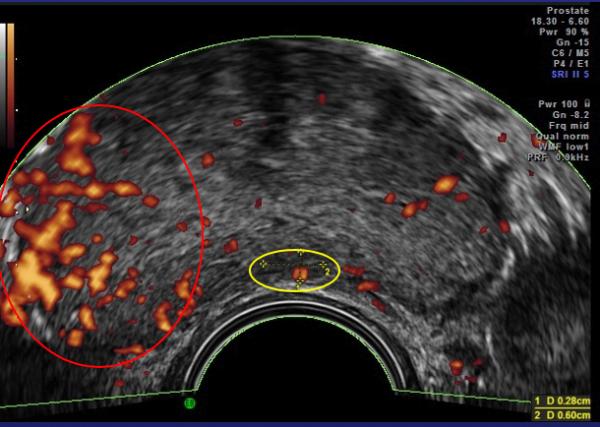

In 1994 Prof. Francois Cornud in Paris developed a better way to sample the tissue of the prostate using Doppler ultrasound. Sound waves are reflected by different tissues at different speeds, creating an image. These doppler images show tumor vascular flow the same way the Weather Doppler shows tornadoes. The presence of tumor-related blood vessels poses a hazard during the biopsy, where they can be inadvertently “nicked,” resulting in bleeding, and their presence indicates a more serious, “aggressive,” tumor. Effective cancer therapies shrink these arteries, making this 10-minute examination both safer and a means of indirectly monitoring treatment.

Since prostate cancer is, in many instances, slow-growing, early cases are often managed by watchful waiting, without invasive surgery or chemotherapy. Ultrasound imaging that detects increased tumor vascularity allows patients with biopsy-proven cancers to come in for regular scans to see if their disease is stable or if more aggressive treatment is indicated.

These technologies can focus the doppler’s sound waves on specific areas and additional data describing blood flow obtained. This data can be combined to generate a quantitative reading of the tumor vessel density to serve as a treatment guide. Vessel density of 15% is found in aggressive cancers requiring intervention, while densities of 1-2% are noted in most low-grade tumors, that can simply be monitored.

chemotherapy are conventional alternatives. It is advisable to seek medical opinions on personalized healing options as side effects occur and treatment is best individually tailored. Recurrence may occur following successful initial therapy with any treatment modality, and Doppler ultrasound with MRI is useful in detecting any regrowth as this image shows.